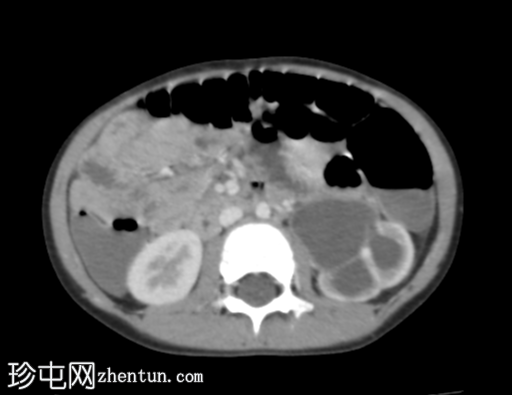

肾轴位

排泄期

左侧肾盂肾盏系统中度扩张;但未见明确的放射性结石。

右肾未见异常。

影像

学表现最可能为左侧肾盂输尿管连接部梗阻。